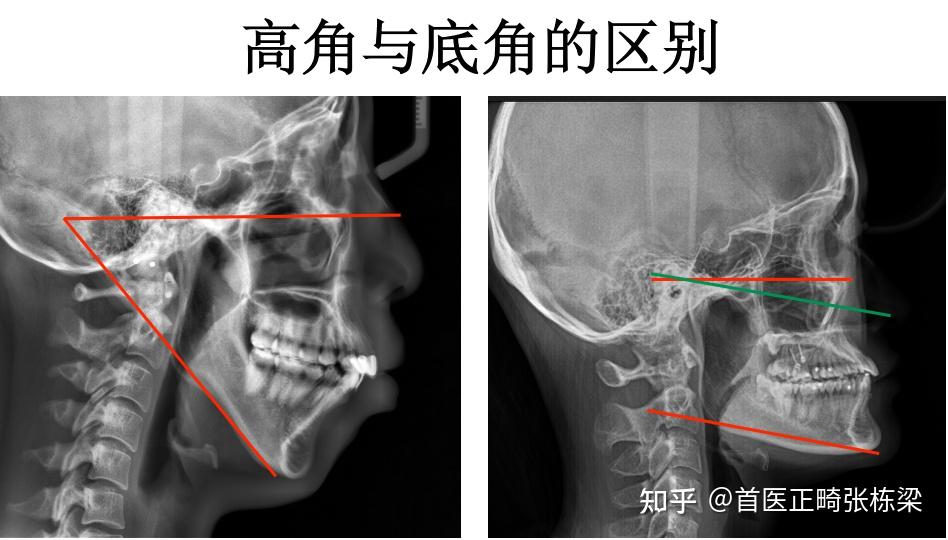

下巴后缩,是指我们下颌骨的形态、大小、位置整个生长发育方向都存在问题,非常典型的就是我们所说的高角、骨性II类的患者,我们可以看到这些患者的下颌骨是呈现一个顺时针的旋转方向在生长的。

还需要控制好后部的颌平面角度,颌平面一定是平的,不能是倾斜的,如果颌平面越斜,会让下巴后缩。